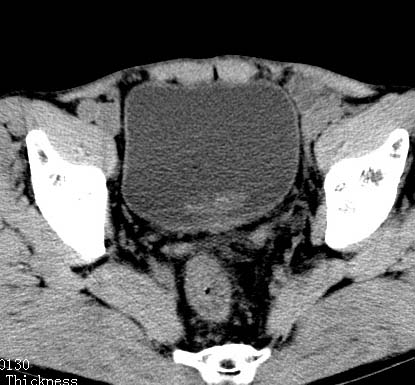

标题: CT17540:男 56岁 . [打印本页]

病人男 56岁 .

前列腺增生,膀胱后壁未见异常,精囊腺及精囊三角未见异常

前列腺增生 钙化!

支持 前列腺增生、钙化。

建议进一步检查除外前列腺癌.

考虑慢性前列腺,精囊炎;不除外前列腺癌

前列腺增生并钙化,可疑直肠占位

前列腺癌.